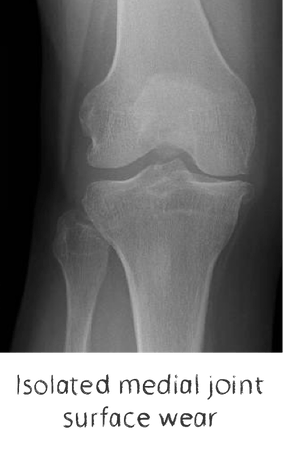

If the knee joint is arthritic in only one of the 3 parts of the knee joint, partial knee replacement is possible, rather than replacing the whole joint.

If the arthritis affects one compartment of the knee and the patient is very young and active, we can sometimes perform osteotomies (bone cuts) and realign the joint to off-load the painful part of the knee joint.